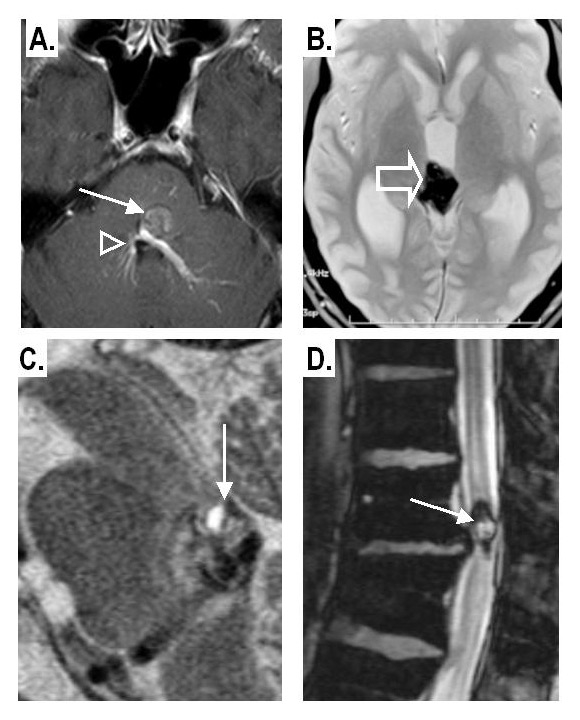

Figure 5

A: Co-existence of a CM in the brainstem (arrow) with a developmental venous anomaly (arrowheads) in the contrast-enhanced T1-weighted image.

B: Intra-ventricular CM: within the third ventricle well seen on a gradient-echo T2* image.

C: Infra-tentorial CM with a “fluid-fluid level” pattern on a sagittal T2-weighted spin-echo image

D: Intra-spinal CM; dark haemosiderin rim on gradient-echo T2* sequence

A total of 728 CM lesions were detected with 69% of lesions having a supra-tentorial localisation: 50.3% in a cerebral hemisphere (fig. 4, 6A,B) and 4.2% in the basal ganglia; 22% were infra-tentorial with 14% in the brainstem (fig. 5A) and 8% in the cerebellum; 3% were spinal (fig. 5D) and 1.5% were orbital (fig. 6C,D, table 3). Multiple lesions were detected in 65 patients (18.9%). These cases had an average of 6.9 lesions per patient. The size of lesions could be calculated in 228 patients who were scanned at our institution and was mostly smaller than 3 cm, with a range from 0.2 to 8 cm (fig. 2E). Symptomatic CMs (average diameter: 1.75 cm, n = 164) were significantly larger (p <.0001) than asymptomatic (average diameter 0.91 cm, n = 64).

The first case of cavernous vascular growth in the brain was documented in 1854 [7]. The first paper on the potentially hereditary nature of the illness (heredofamilial angiomatosis) was published in 1928 [8]. Cavernous malformations are single or multiple mulberry-like masses of closely apposed immature blood vessels (“caverns”) lined by a thin endothelium, and lacking muscle cells, elastic fibres and intervening parenchyma. Usually no sizeable feeding or draining vessels are located within or in close vicinity to a CM, making it a low-flow “angioma” often occult on conventional angiography [9]. Acute or organised thrombi are usually found in CMs. Chronic small bleeds lead to a gliotic layer stained with haemosiderin around the lesion. Cavernous malformations are characteristically “dynamic” [10]. Recurrent haemorrhages and thromboses as well as cyst formation in a lesion can lead to lesion growth, with a size up to 10 cm, and may cause pressure on the surrounding brain parenchyma [11–13]. They may also shrink significantly but rarely remain quiescent. Rare subtypes include the cystic type, the extra-axial type (fig. 5B) and the calcified haemangioma type [14].

CT has a sensitivity of 36–74% [21, 24] to detect CMs by exhibiting a space-occupying effect, focal nodular hyperdensity and calcifications on unenhanced CT and mild enhancement on CT after intravenous iodinated agents [25]. MRI remains the method of choice for the detection of CMs. The signal behaviour is determined by the stage of bleeding or thrombus and thus the haemoglobin form in the lesion. Characteristic appearances include the “popcorn” as well as the rare “fluid-fluid level” pattern (fig. 5C). The susceptibility-weighted MRI uses the “blooming effect” due to the susceptibility effects of the blood by-products to enhance lesion detectability (fig. 4B). CMs present with variable degrees of contrast enhancement and, thus, are definitely not distinguishable from AVM when assessed with contrast-enhanced MRI (fig. 5A) [26]. A classification of CMs based on MRI was originally proposed by Zabramski [27, 28].